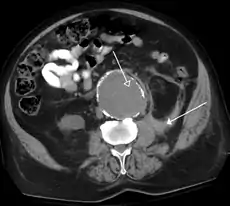

A CT scan image showing a ruptured abdominal aortic aneurysm.